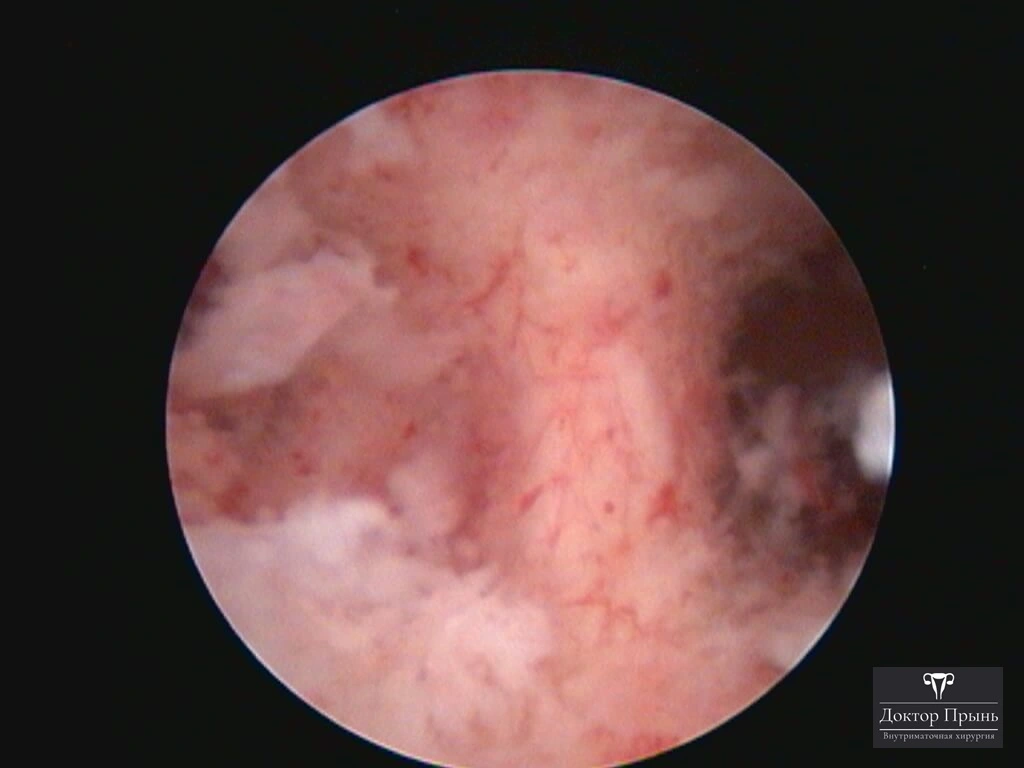

Это спайки в полости матки, которые возникают после внутриматочных вмешательств: выскабливаний, особенно после родов, абортов, удаления субмукозной миомы. Степень выраженности спаек варьируется от единичных лёгких перетяжек до полного заполнения полости матки плотной рубцовой тканью. Также спайки появляются в цервикальном канале.

Как правило, синехии находят при УЗИ. Когда по УЗИ патологии нет, а симптомы есть, выполняют гистероскопию – это золотой стандарт в определении синехий.

Гистероскопия позволяет не только увидеть спайки, но и сразу вылечить, т.е. рассечь их. Большинству пациенток подойдёт офисная гистероскопия без наркоза и госпитализации. Среднее время операции 15 минут. Иногда требуется 2-4 операции, чтобы восстановить полость матки.

Крайне важен способ разделения спаек. Если это холодный инструмент, например, ножницы, то вероятность рецидива низкая. Плюс не повреждается нормальный эндометрий. Если рассекают горячей электропетлёй, то, наоборот, риск рецидива высокий и можно обжечь эндометрий.

Фотогалерея

Синехии, рассечённые Прынь Д.В.